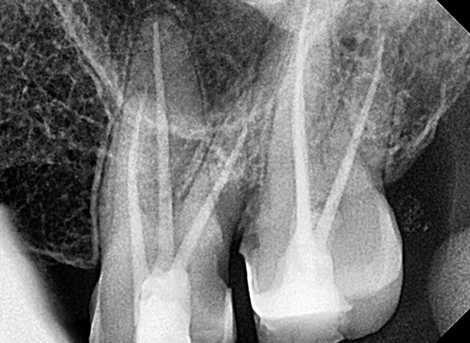

Complete disinfection of the root canal.

Laser Cleaning